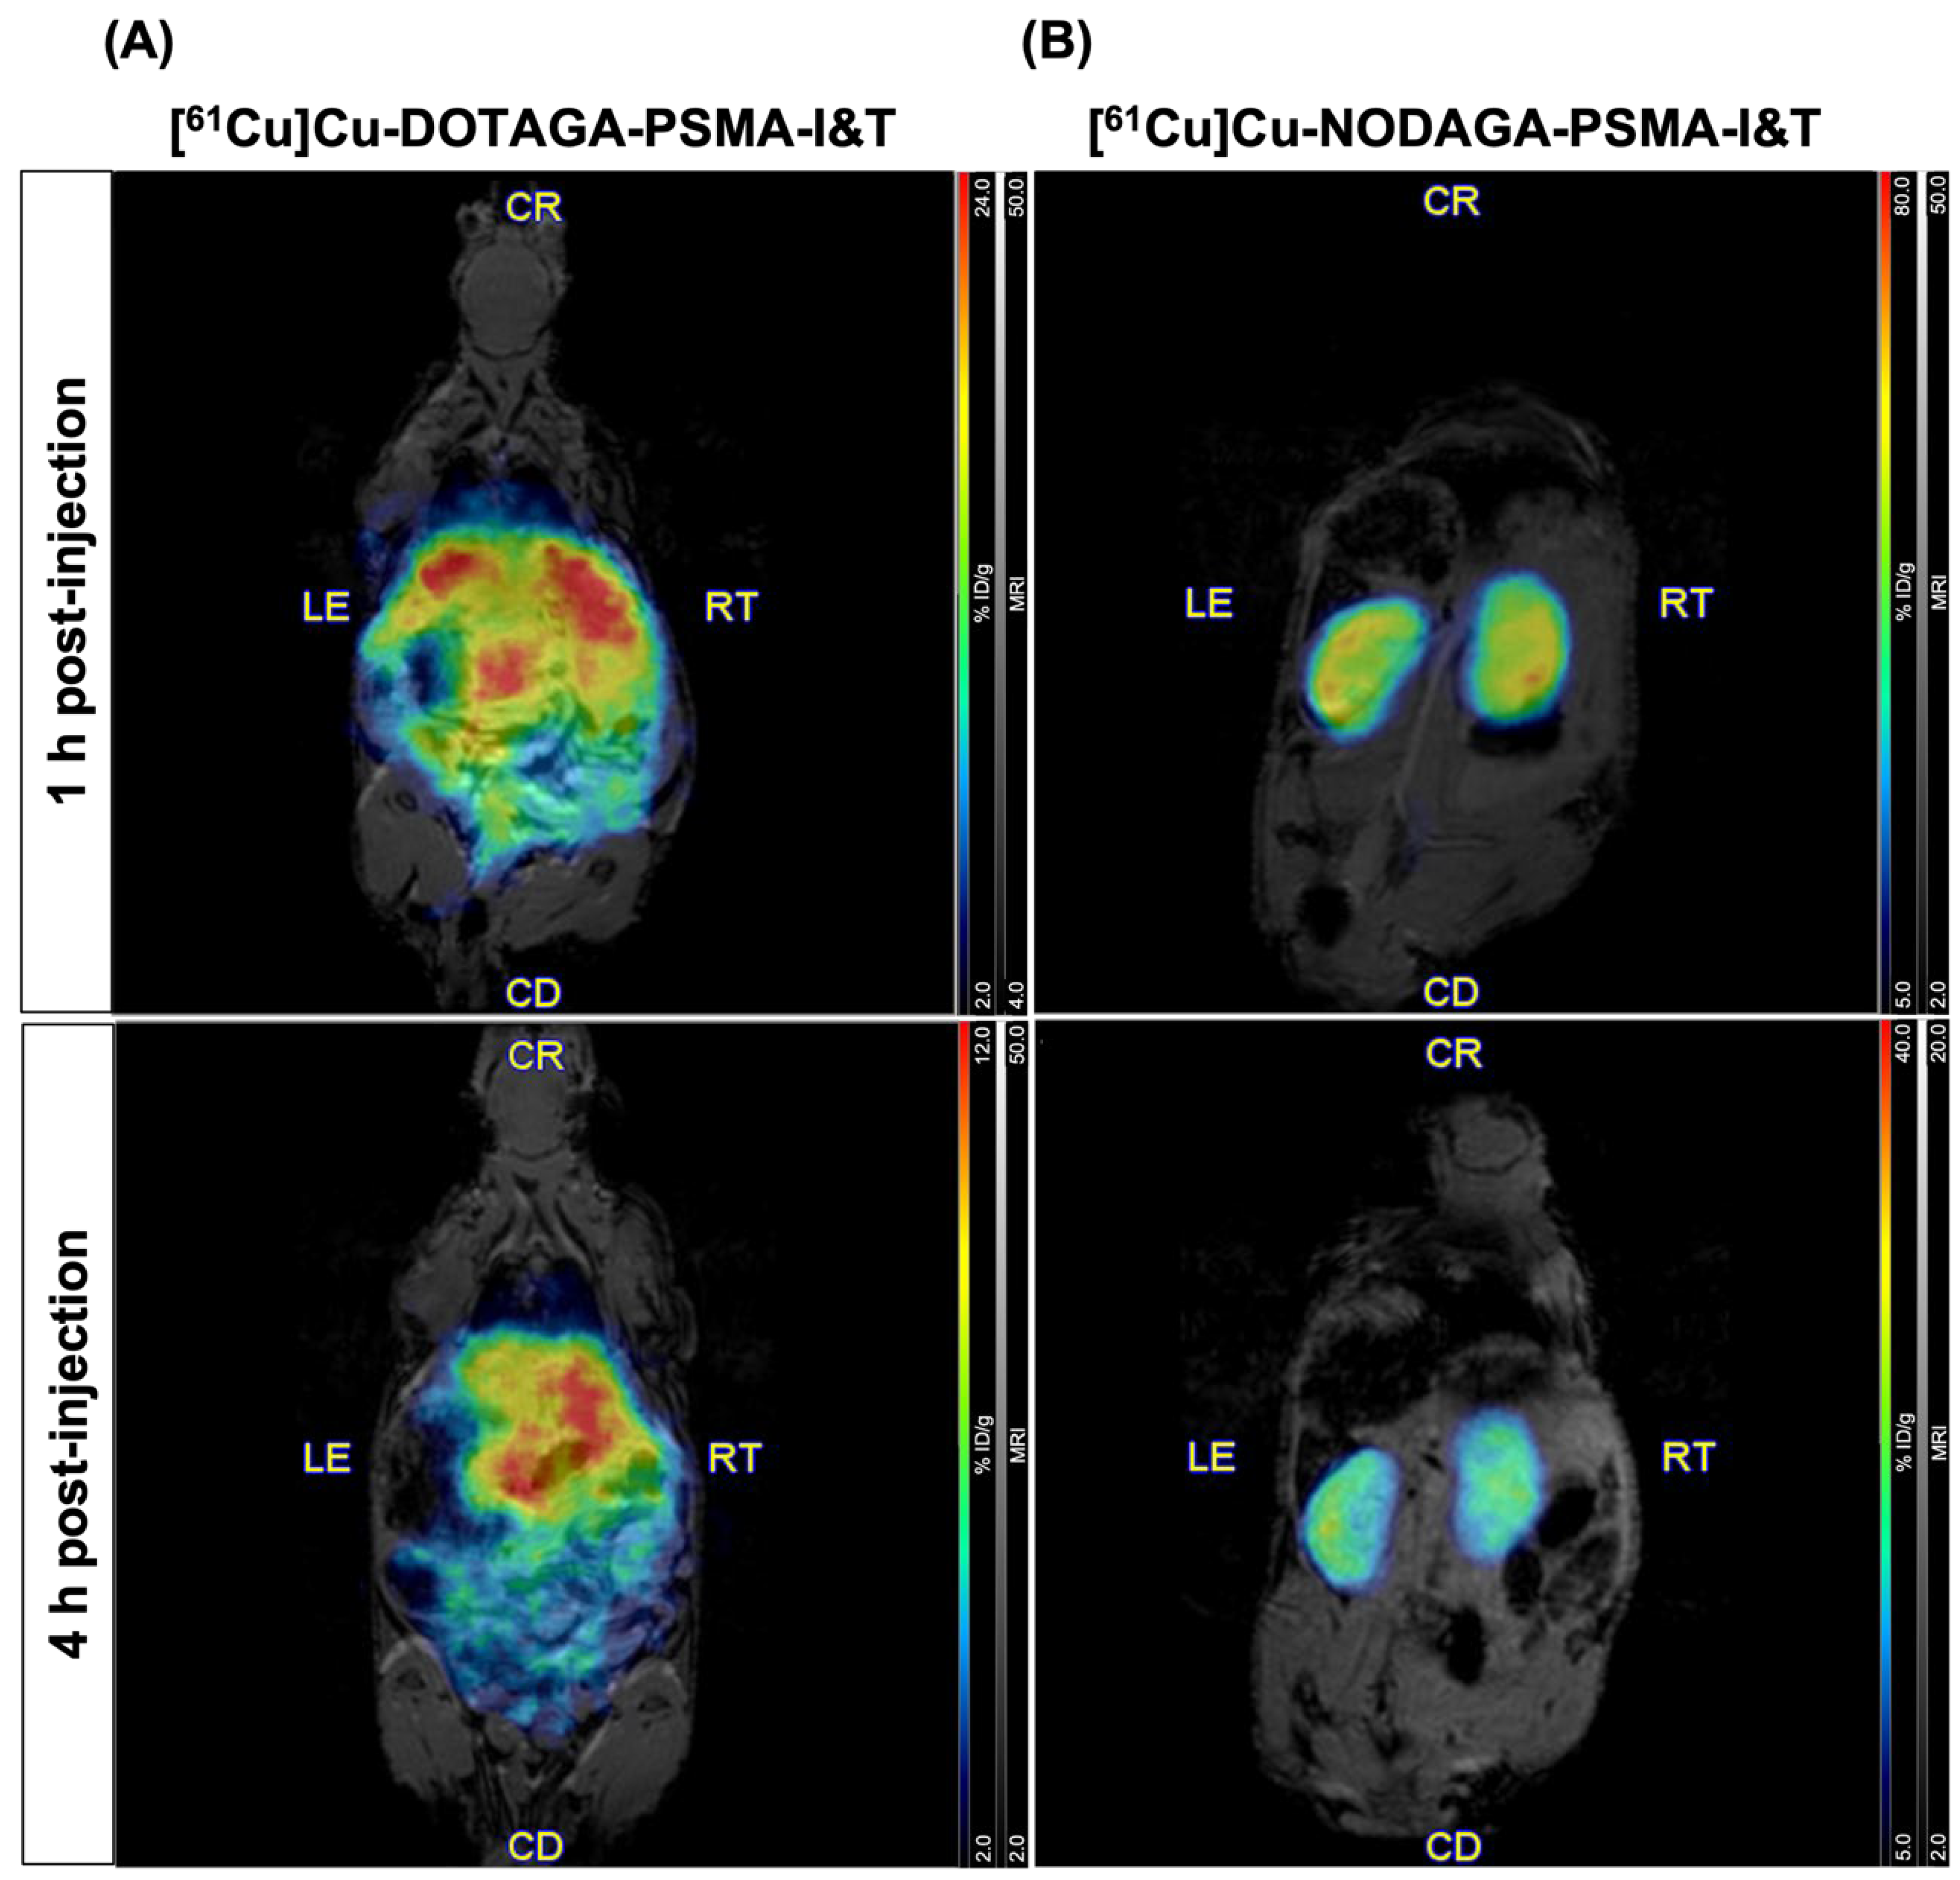

2.3. PET/MR Imaging in Healthy Mice